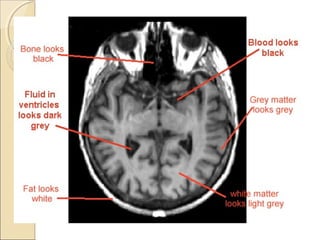

T1 & T2 W IMAGINGT1 & T2 W IMAGING

CT SCAN

MRI T1 Weighted

MRI T2 Weighted

MRI T2 Flair